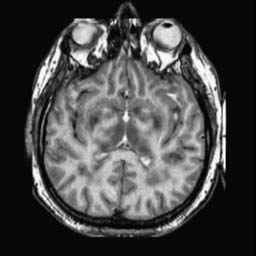

To demonstrate the effectiveness and efficiency of the proposed image fusion method , we conduct a set of comparative experiments on three image datasets. The first is composed by 8 pairs of multi-modal medical images and the second one contains 15 pairs of multi-focus gray or color natural images. These two datasets are often used in many related papers and some examples are shown in Figure 3(a) and Figure 3(b). The third one is a new multi-focus cervical cell image dataset collected by ourselves, which consists of 15 groups of color images and each group contains a series of multi-focus cervix cell images with size of or , etc. Some source examples are shown in Figure 3(c). Our source code implemented in C++ along with the new multi-focus cervical cell image dataset is available online.

We first evaluate the performance of the proposed method under varying total number of octaves and number of layers sampled per octave. The fused images of a pair of multi-modal medical images with different and are shown in Figure 4. In this example, on the one hand, when only 1 or 2 octaves are involved in constructing the DoG pyramid, the fused images fail to keep the integrity information of large size objects (e.g. eyeballs), while by increasing the value of , the integrity information of eyeballs is preserved. On the other hand, although not as significant as the increase of octave numbers , the fused image can contain more details by the increase of layer numbers . The corresponding objective quality metrics are shown in Figure 5. As shown in Figure 5(a), most of the metric values are improved as the number of octaves increases with the fixed layer numbers 3 in the global tendency and each of them tends to be stable when the number of octaves is 5. To get a relatively good quality from Figure 5(b), we can notice that some of the metric values can get a good performance when the number of layers is 3, such as the MI, SSIM, QI and VIF, though there are only a little change of all the metric values by increasing the number of layers with the fixed octave numbers 5. Because it will result in more computation burden with the increase of the value and , and for different kinds of source images, there are different performance with the diverse parameter settings. To get a trade-off between them in our experiments, we set for the multi-modal dataset, for the natural datasets and for the multi-focus cell dataset, respectively.

Figure 6 shows the fused images obtained by different methods with the multi-modal source images shown in Figure 3(a). As shown in these figures, the proposed method can produce images which preserve the complementary information of different source images well. Moreover, due to the scale-invariant structure saliency selection, our method can keep the integrity information of large size objects and the visual details simultaneously. Although the fused image generated by other methods can also capture the details to some extent, all of them fail to keep the integrity information of large size objects such as the eyeballs. Furthermore, from Figure 6(k)-6(t), the DTCWT, GFF, IM and NSCT methods may decrease the brightness and contrast while the proposed method can preserve these features and details without producing visible artifacts and brightness distortions.